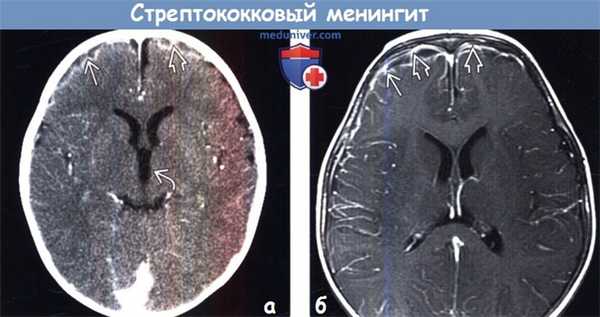

(а) КТ с контрастированием, аксиальный срез: у младенца с β-стрептококковым менингитом определяется контрастирование коры и лептоменинкс Обратите внимание на расширение передних рогов и III желудочка, что отражает нарушение циркуляции СМЖ.

(б) МРТ у того же пациента, выполненное по поводу эпилептического статуса, возникшего спустя 24 часа после КТ, постконтрастное Т1-ВИ, аксиальный срез: данный метод исследования позволяет более отчетливо визуализировать контрастирование коры и лептоменинкс по периферии лобных долей. При исследовании СМЖ с окраской по Граму были выявлены грамположительные диплококки.